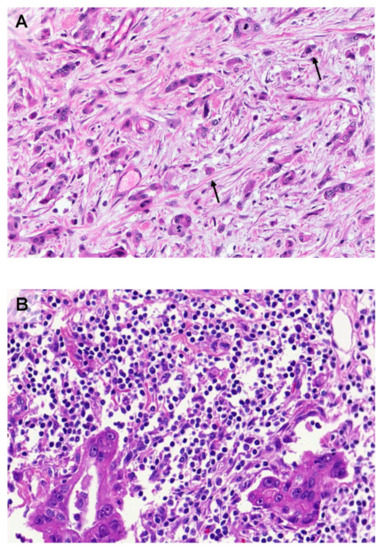

4. Heterogeneity of Immune Cell Composition in the TME of Pancreatic Cancer

- Carstens, J.L.; Correa de Sampaio, P.; Yang, D.; Barua, S.; Wang, H.; Rao, A.; Allison, J.P.; LeBleu, V.S.; Kalluri, R. Spatial computation of intratumoral T cells correlates with survival of patients with pancreatic cancer. Nat. Commun. 2017, 8, 15095. [Google Scholar] [CrossRef] [PubMed]

- Wartenberg, M.; Cibin, S.; Zlobec, I.; Vassella, E.; Eppenberger-Castori, S.M.M.; Terracciano, L.; Worni, M.; Gloor, B.; Perren, A.; Karamitopoulou, E. Integrated genomic and immunophenotypic classification of pancreatic cancer reveals three distinct subtypes with prognostic/predictive significance. Clin. Cancer Res. 2018, 24, 4444–4454. [Google Scholar] [CrossRef]

- Castino, G.F.; Cortese, N.; Capretti, G.; Serio, S.; Di Caro, G.; Mineri, R.; Magrini, E.; Grizzi, F.; Cappello, P.; Novelli, F.; et al. Spatial distribution of B cells predicts prognosis in human pancreatic adenocarcinoma. Oncoimmunology 2016, 5, e1085147. [Google Scholar] [CrossRef] [PubMed]

- Ene-Obong, A.; Clear, A.J.; Watt, J.; Wang, J.; Fatah, R.; Riches, J.C.; Marshall, J.F.; Chin-Aleong, J.; Chelala, C.; Gribben, J.G.; et al. Activated pancreatic stellate cells sequester CD8+ T cells to reduce their infiltration of the juxtatumoral compartment of pancreatic ductal adenocarcinoma. Gastroenterology 2013, 145, 1121–1132. [Google Scholar] [CrossRef] [PubMed]

- Wartenberg, M.; Zlobec, I.; Perren, A.; Koelzer, V.H.; Lugli, A.; Karamitopoulou, E. Accumulation of FOXP3+T-cells in the tumor microenvironment is associated with an epithelial-mesenchymal-transition-type tumor budding phenotype and is an independent prognostic factor in surgically resected pancreatic ductal adenocarcinoma. Oncotarget 2015, 6, 4190–4201. [Google Scholar] [CrossRef]